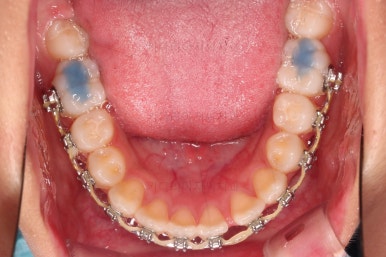

1. 초진 시 입안의 모습 평가

부산치아교정치과 키다리아저씨치과에 처음 내원했을 당시의 입 안의 모습입니다.

전반적으로 윗니가 나와있는 양상이고요.

앞니는 뻐드러져 있네요.

아래 앞니는 위로 솟구쳐 올라서 윗니 뒤쪽을 강하게 치고 있는 과개교합 양상이었고요.

위아래 앞니쪽이 삐뚤어져 있는 상태였습니다.

우선 윗니만 장치를 부착했습니다.

순서는 윗니 장치 부착 후 발치를 하고, 가지런하게 된 뒤에, 과개교합 개선을 위한 특별한 장치가 들어가면서 아랫니에도 브라켓을 부착하기로 정했습니다.

이번 환자분이 선택한 장치는 엠파워 메탈이라고 하는 자가결찰 금속 브라켓입니다.

윗니가 가지런해진 뒤에는 부산치아교정치과 키다리아저씨치과에서는 ABP라고 하는 장치를 사용해 주면서 아랫니에도 브라켓을 부착합니다.

깊게 물리는 과개교합을 개선하기 위함인데요.